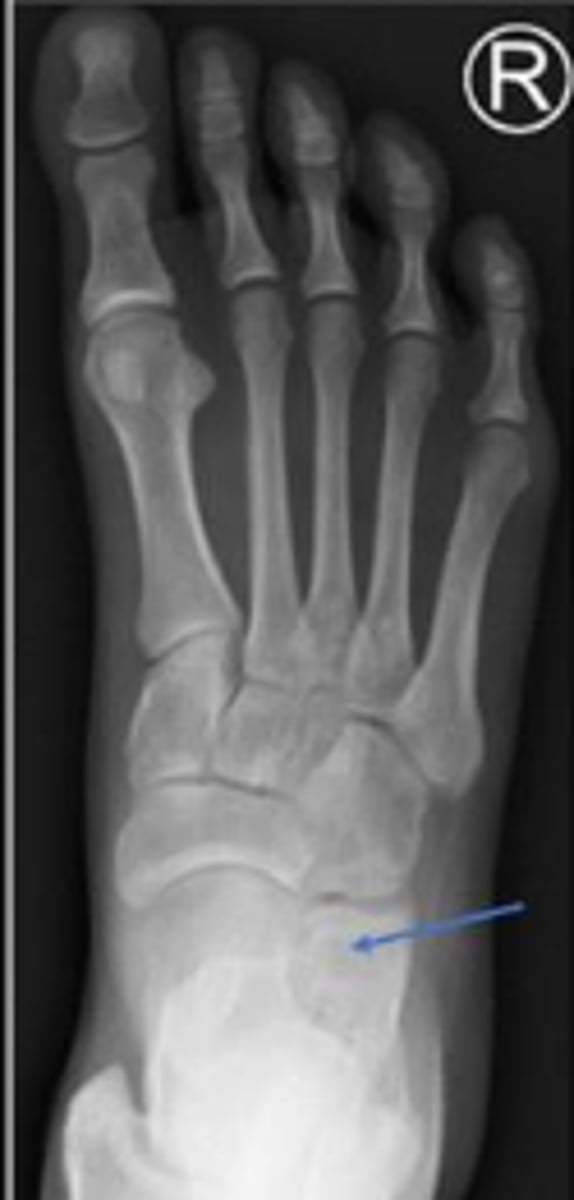

AP right foot

What is the name of the radiographic view?

Cuboid of the right foot

What are the arrows pointing to?

2nd metatarsal of the right foot

Sesamoid bones of the right foot within the tendon of the flexor hallicus brevis